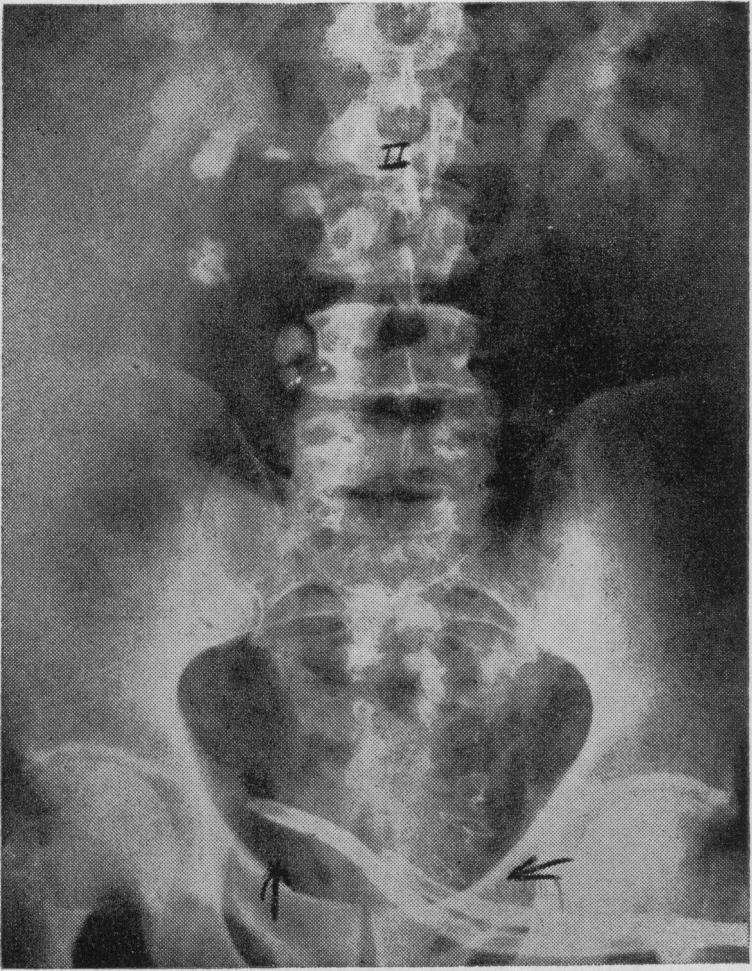

Sigmoid segment substitutes for bladder.